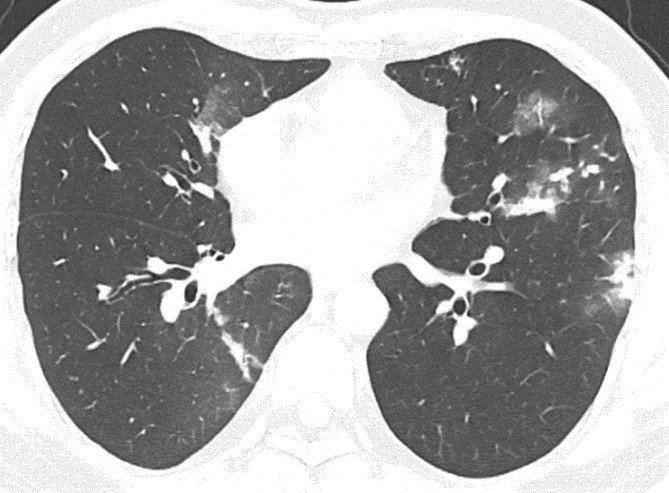

Chụp CT lồng ngực kết luận hình ảnh đông đặc và nốt mờ hai phổi, có phá hủy tạo hang thùy trên phổi (theo dõi tổn thương do lao), hạch trung thất, thoái hóa cột sống ngực.